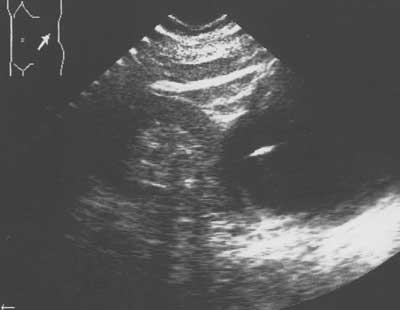

Рис. 3. Эхограмма левой почки. В просвете кисты видна тень пункционной иглы. В процессе эвакуации содержимого из кисты стала определяться левая почка.